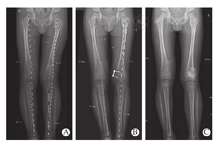

术前常规拍摄膝关节平片,了解局部病变范围及骺板的生长潜力。为了评价下肢畸形的严重程度、变化趋势和矫正效果,术前和术后随访时均拍摄下肢全长测量片,测量股骨远端解剖轴外侧角(anatomical lateral distal femoral angle,aLDFA)、胫骨近端内侧角(medial proximal tibial angle,MPTA)和下肢机械轴的偏离度(mechanical axis deviation,MAD)[10]。本组中采用膝关节分区法[6,11]来评价MAD(图1)。如果下肢机械轴超出-1~+1区间,同时股骨远端或胫骨近端骺板存在至少2年的生长潜力(男孩<14岁,女孩<12岁),是应用临时性骺阻滞的手术适应证。

15例股骨术前aLDFA:65.5°~79.4°(平均76.2°),取板时aLDFA:72.6°~88.5°(平均83.7°),外翻角度改善明显(P<0.001)。13例胫外翻术前MPTA:90.5°~100.4°(平均95.7°),取板时MPTA:83.1°~92.7°(平均88.7°),外翻角度明显改善(P<0.001)。1例胫内翻术前MPTA:83°,取板时MPTA:88.4°。15例股骨外翻角度改善5.1°~11.4°(平均7.5°),13例胫骨外翻角度改善2.3°~14.5°(平均7.0°),两者差异无统计学意义(P=0.472)(表2)。1例男孩,13.5岁时行右股骨和胫骨骺阻滞,带板共31个月,股骨外翻角度改善7.1°,胫骨外翻角度改善2.9°。骺板闭合后仍残留外翻畸形,16.1岁时取出8字板、同时行截骨矫形术。除此例外,14例股骨矫正速率为0.3°~1.1°/月(平均0.6°/月),12例胫骨矫正速率为0.2°~1.0°/月(平均0.5°/月)。两者差异无统计学意义(P=0.151)。19例膝中,术前下肢机械轴3例(15.8%)位于膝关节+3区,16例(84.2%)位于+2区。取板时17例位于-1~+1区,下肢力线恢复正常,1例位于+3区,1例位于-2区,优良率达89.5%(图2)。

手术共包括29例长骨(15例股骨和14例胫骨),取板后随诊时间超过6个月共计22例阻滞骨(14膝)。其中,11例取板后角度测量值无明显变化,共有7男4女,取板时的年龄分别为12.7~14.5岁(平均13.7岁)和12.2~12.4岁(平均12.3岁)。11例外翻角度出现反弹(图3),共有9男2女,取板时的年龄分别为5.1~12.7岁(平均10.6岁)和8.5岁。其中股骨5例,末次随访aLDFA:80.4°~85.3°(平均82.3°),较取板时减小3.2°~5.6°(平均4.1°);胫骨6例,末次随访MPTA:87.3°~98.3°(平均93.2°),较取板时增加4.1°~7.5°(平均5.3°)。14膝中,取板时下肢机械轴6例位于+1区,7例位于-1区,1例位于-2区。末次随访时1例位于+2区,11例位于+1区,2例位于-1区。其中6例分区无变化,6例从-1区移入+1区,虽然外翻角度有反弹,但下肢力线仍处于正常范围,优良率达92.9%。1例8.5岁患儿,右股骨和胫骨骺阻滞术后未定期随诊。术后14个月复查,下肢已轻度内翻,机械轴位于-2区,取板后11个月机械轴恢复到-1区。另1例7.7岁患儿行左胫骨骺阻滞,取板时机械轴位于+1区。23个月后胫外翻复发,机械轴又回到+2区,于10.7岁时再次行骺阻滞术。本组除此例畸形复发外,未出现骺板生长抑制、螺钉回退或松动、钢板或螺钉断裂、伤口或骨感染和关节活动受限等并发症。